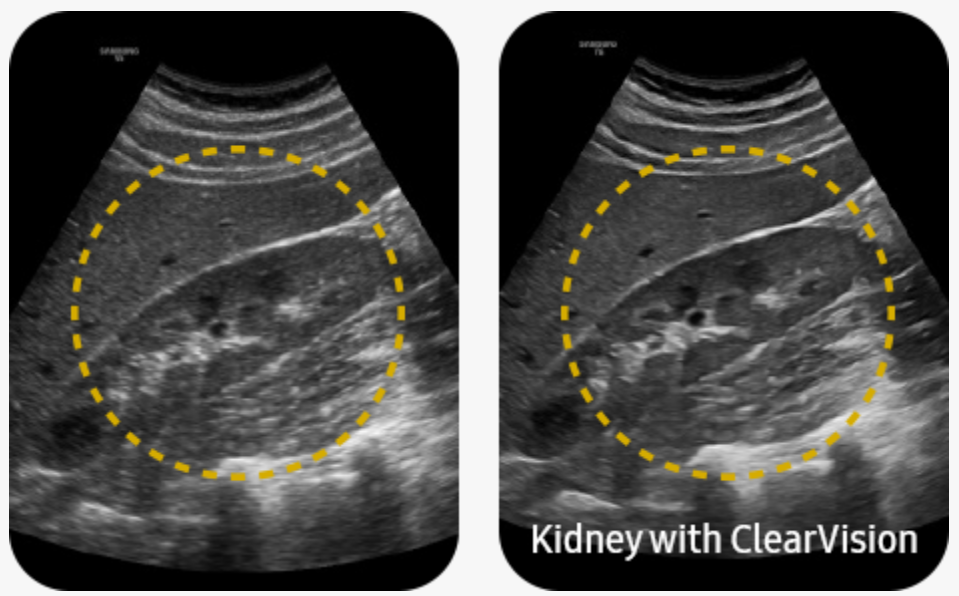

Zlepšení kvality obrazu díky redukci šumu |

ClearVision redukuje šum a zlepšuje vykreslení hran a vytváří tak ostré 2D obrazy pro optimální diagnostiku. ClearVision navíc poskytuje optimalizaci pro konkrétní aplikace a pokročilé časové rozlišení v režimu živého skenování.